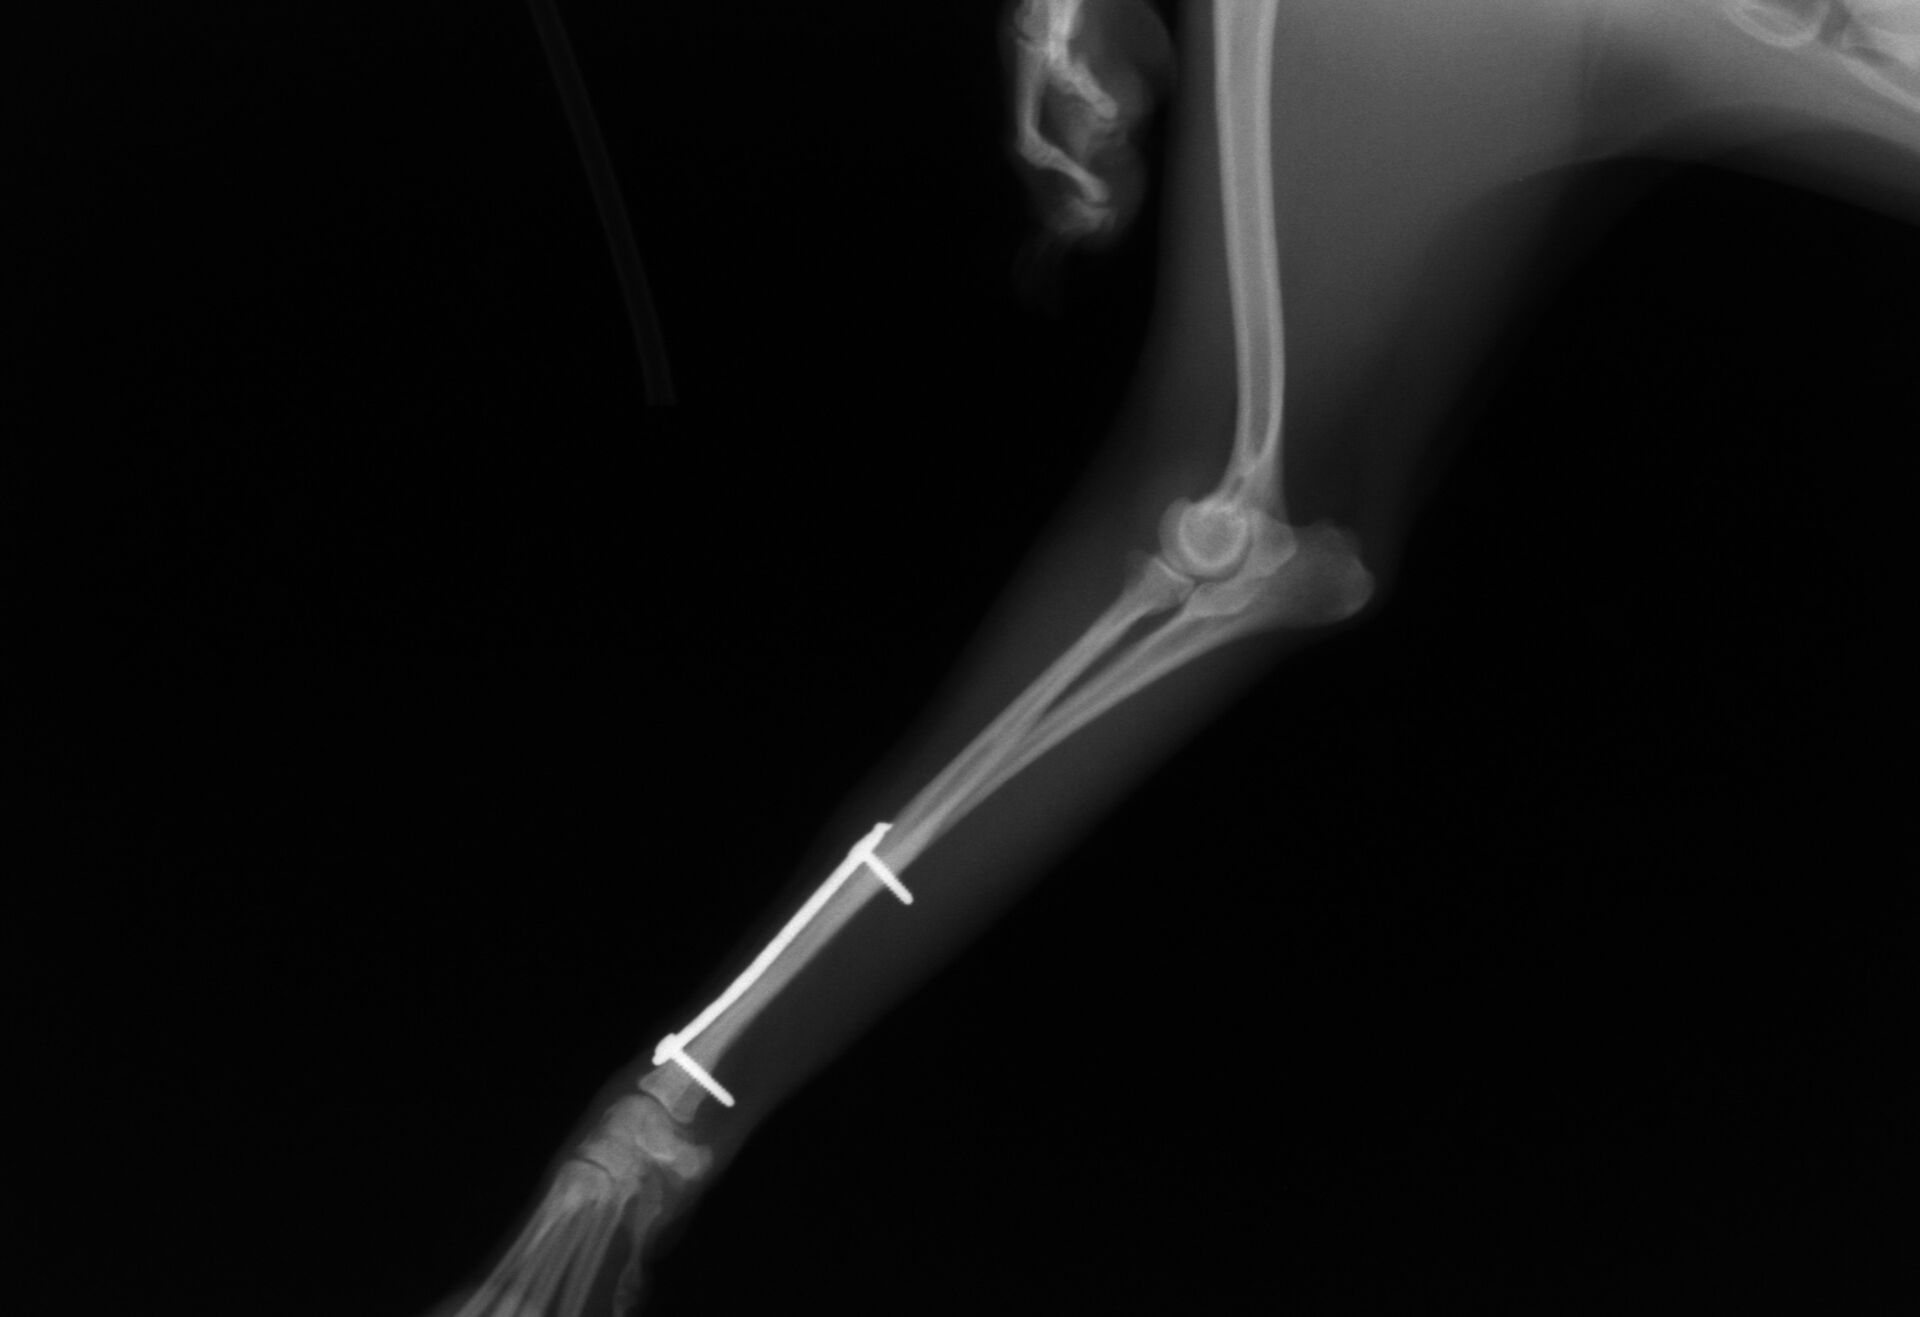

その後、1か月普通に生活していました。レントゲンを撮ったところ、骨は十分に増生していたので、心配ないと判断しプレートを取りました。

プレート除去前

プレート除去後

プレート除去後は何の問題もなく生活しています。うまくいきました。